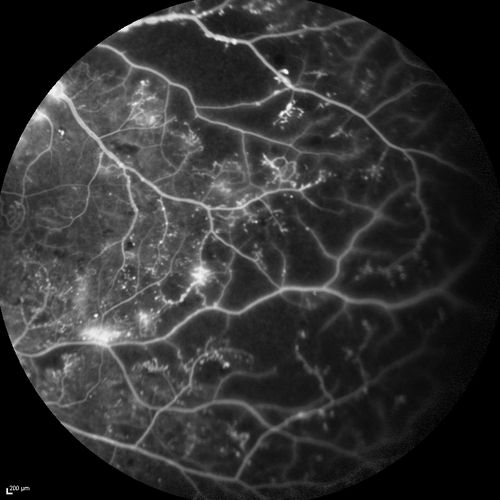

Proliferative Diabetic Retinopathy - Moderate - mild NVD with NVE

FA shows leakage from neovascularization and dark areas in periphery from non-perfusion